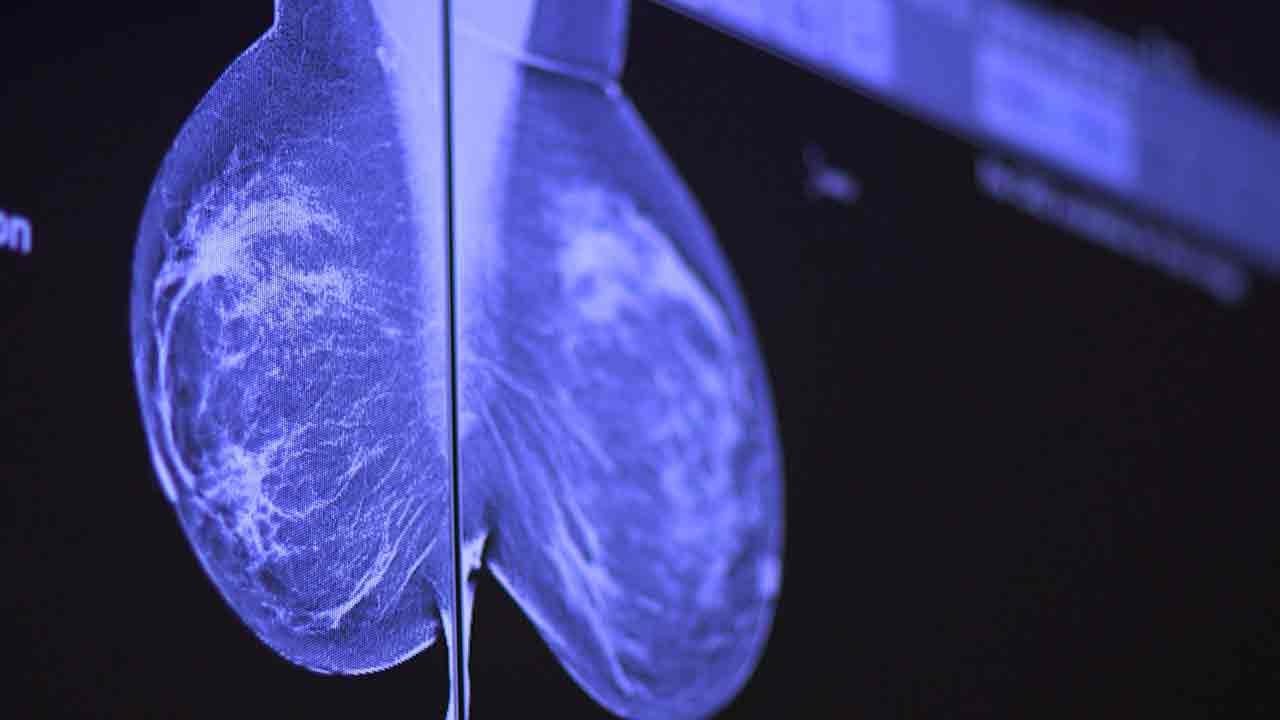

At Stanford, we offer you the most advanced diagnosis and treatment techniques for breast cancer, no matter how common or complex your cancer type. Our program is a major referral center for women and men across the country.